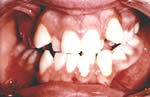

If your child develops an "open bite", or you are otherwise concerned about the development of your child's teeth, no matter what the age, contact us right away for a consultation with Dr. Prather. Otherwise, children should be evaluated by the age of 6 for orthodontic treatment. In the past, a child was 11 or 12 before brackets were actually placed on the teeth to straighten them. This may still hold true in most cases, but there are new techniques that can correct problems early, while a child is still growing. This may eliminate the need for braces in the future, or if the child does still need braces, the treatment will be less complicated, usually shortening the period of time in braces.

before teeth

Before